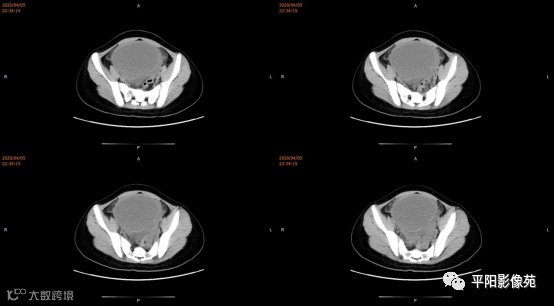

3.CT检查 对子宫、阴道的界限区分有一定限制,对子宫内膜、肌层难以分辨,故CT对子宫先天性异常的研究较少。阴道闭锁时,若宫腔内经血潴留,可见液性低密度聚集,子宫肌层密度均匀。